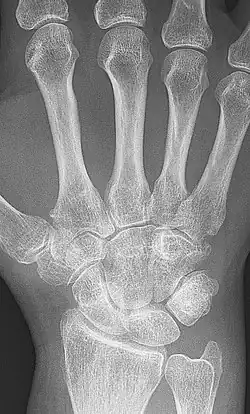

X-rays of the hands and feet are generally performed when many joints are affected. In RA, there may be no changes in the early stages of the disease, or the X-ray may show osteopenia near the joint, soft tissue swelling, and a smaller than normal joint space. As the disease advances, there may be bony erosions and subluxation. Other medical imaging techniques such as magnetic resonance imaging (MRI) and ultrasound are also used in RA.[20][79]